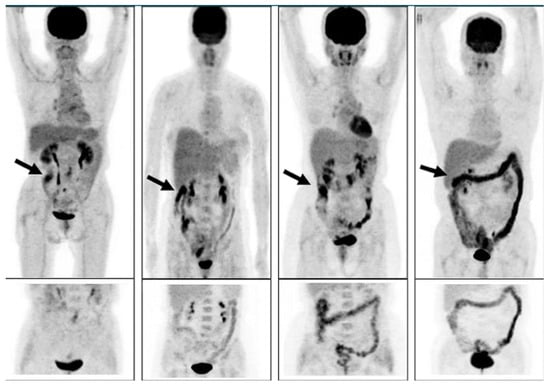

Morita and coworkers [171], by using positron emission tomography (PET)-MRI, recently found that the maximum standardized uptake value (SUVmax) of F18-FDG in the intestine (jejunum, ileum, and right or left hemicolon) of metformin-treated diabetics was higher than that of the control group. More importantly, the study permitted to differentiate the SUVmax of the intestinal wall from that of the intestinal lumen. The SUVmax of the intraluminal space in metformin-treated diabetics was greater than that of the controls (Figure 2). On the contrary, the SUVmax of the intestinal wall was similar in both groups [171]. A temporarily increased accumulation of the injected tracer seems to be observed (Figure 3) also in the liver of metformin-treated diabetics up to 48 h after interruption of the oral uptake of the drug [171,172,173], suggesting a persisting uptake of the radioactive glucose mediated by circulating insulin as consequence of the “metabolic starvation”(?) induced by the biguanide.

Figure 3.

PET scan was performed in diabetics at different times after interruption of metformin therapy. In patient 4, interruption time was shorter than 48 h and showed strong accumulation of the tracer in the colon. From Schreuder N et al. [173].

Accumulation of F18-FDG in the large intestine (Figure 4) has been found also in persons who regularly use laxatives [175,176]. SUVmax can even reach levels that simulate those of colorectal neoplasms (Figure 5) in patients with chronic constipation [177].

Figure 4.

PET pictures of early scans (upper row) and of late FDG scans (lower row) after oral administration of laxatives. The arrows in the upper row of PET scans show the different patterns of accumulation of the tracers in the large intestine. From Chen Y-K et al. ([176], with permission).